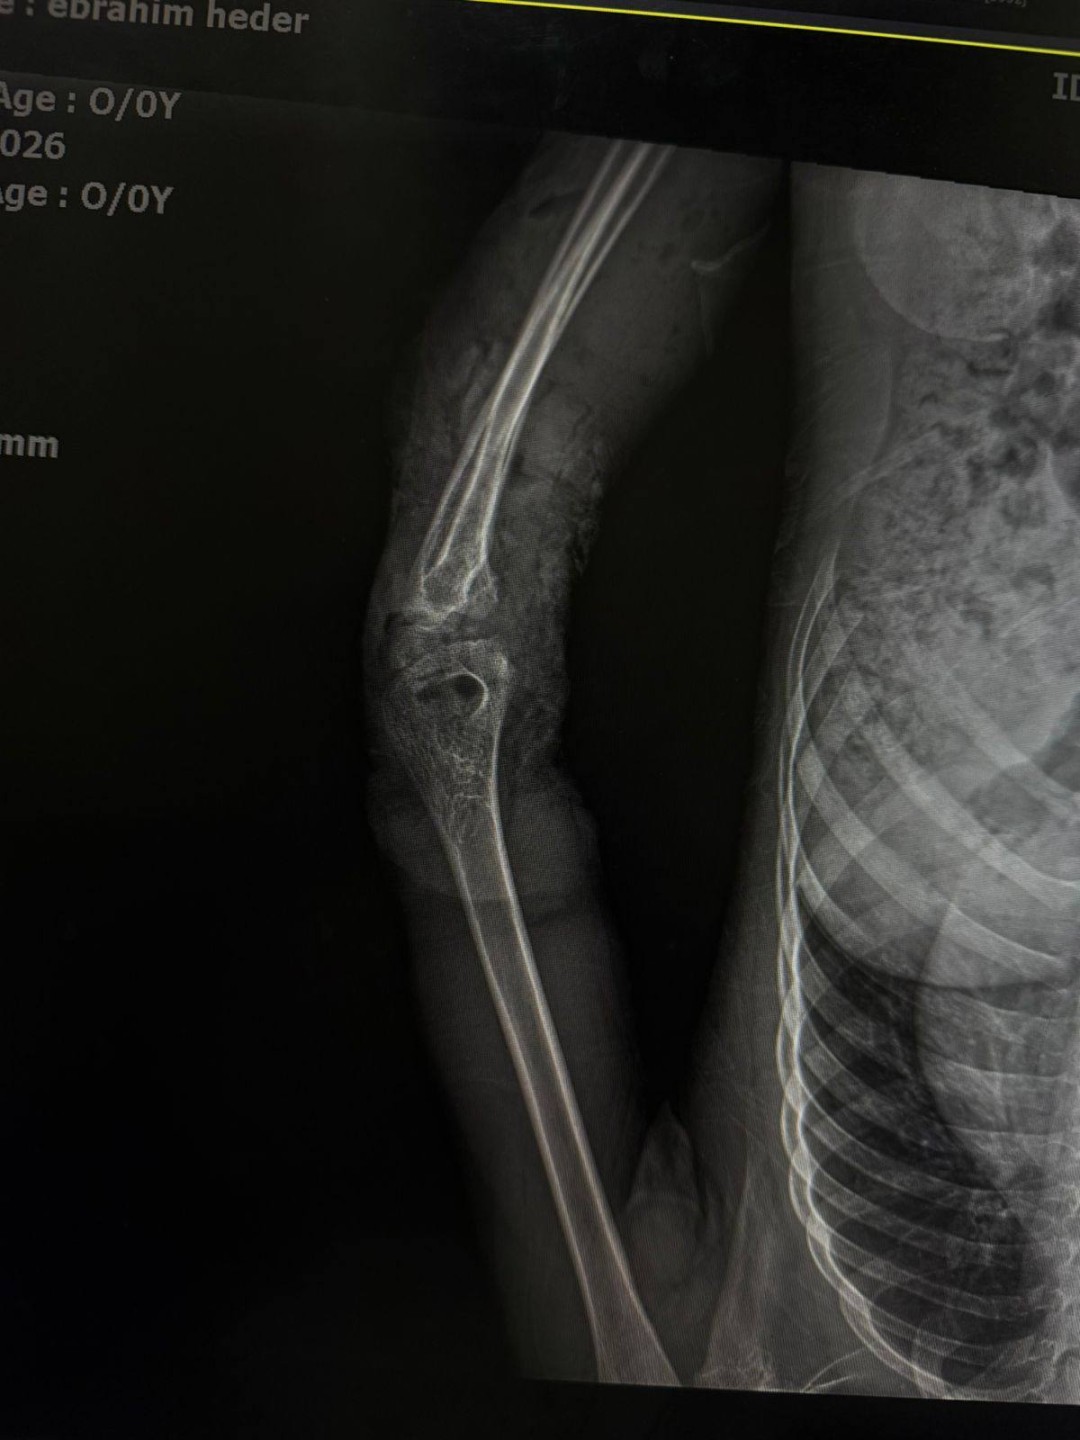

نجح فريق طبي متخصص بمستشفى الطوارئ الجديد بجامعة سوهاج، في إنقاذ ذراع طفل يبلغ من العمر 12 عامًا، عقب تعرضه لإصابة شديدة نتيجة حادث طاحونة قمح، أسفر عن تهتك كامل بأنسجة الذراع، وكسور متعددة بالأصابع، إلى جانب إصابة الأوتار والأعصاب.

وأوضح الدكتور مجدي القاضي ، عميد كلية الطب ورئيس مجلس إدارة المستشفيات الجامعية ، أنه فور وصول الطفل إلى مستشفى الطوارئ، تم إدخاله إلى غرفة الإنعاش لاستقرار الوظائف الحيوية، ثم نقله مباشرة إلى غرفة العمليات، حيث شارك فريق طبي متكامل من وحدة جراحات اليد الميكروسكوبية، وجراحة التجميل، والتخدير في إجراء تدخل جراحي دقيق ومعقد.

وأشار الدكتور أحمد كمال، المدير التنفيذي للمستشفيات الجامعية ، إلى أن فريق وحدة جراحات اليد الميكروسكوبية قام بتثبيت الكسور الدقيقة بالأصابع، وتوصيل الأوتار والأعصاب المصابة، مع استكشاف الأوعية الدموية والتأكد من سلامتها، فيما تولى فريق جراحة التجميل إجراء رقعة جلدية لتعويض الجزء المتهتك المفقود من الذراع.